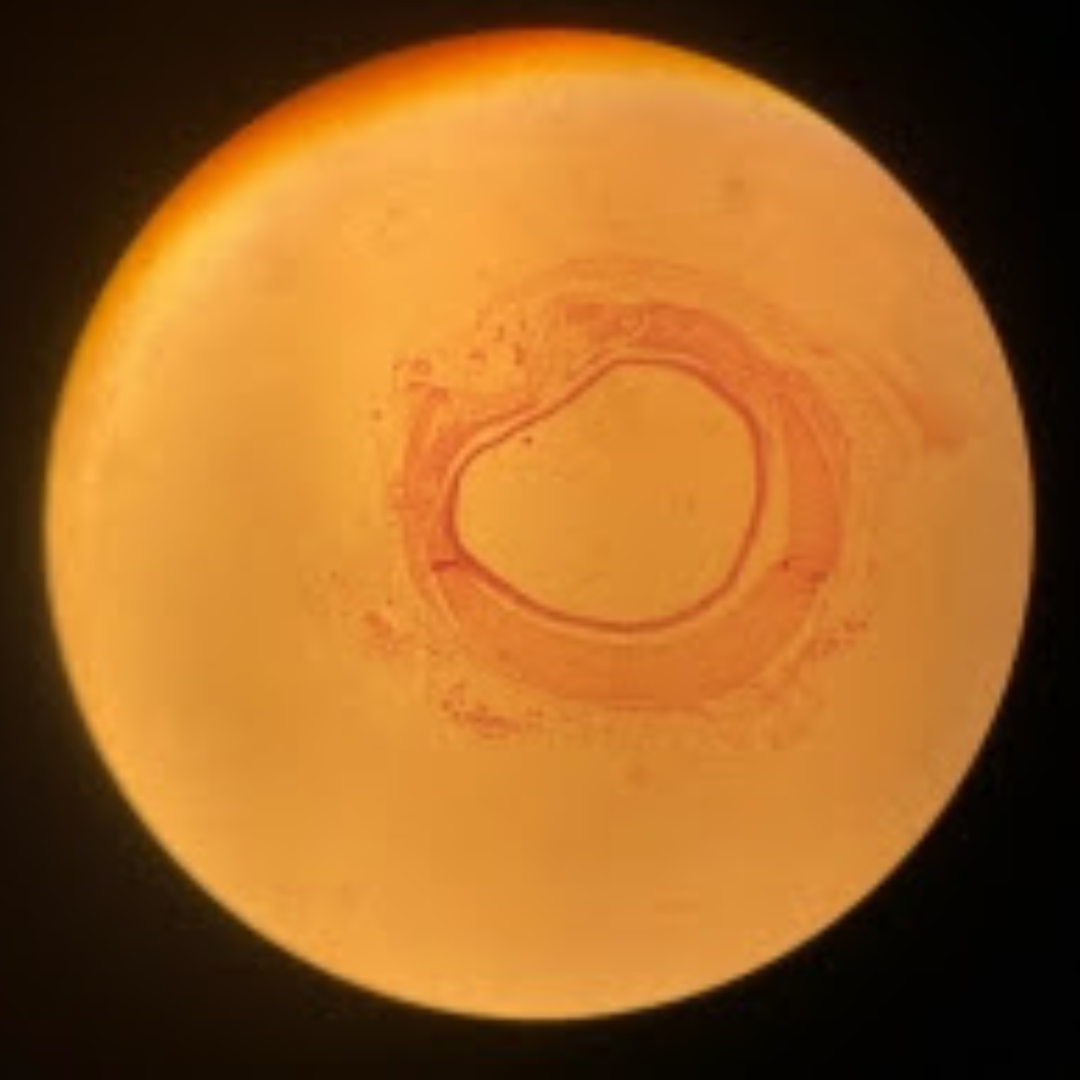

Muscular Arteries (Medium Sized Arteries)

Muscular Arteries (Medium Sized Arteries)

Muscular Arteries (Medium Sized Arteries)